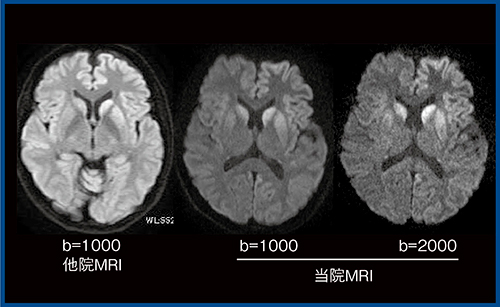

1.高b値撮像の有用性

拡散強調画像は,1.5T MRIではb=1000s/mm2程度,3T MRIではb=2000〜3000s/mm2程度の高b値にすることで,正常皮質のコントラストが低下し,病変の視認性が向上する。これにより,クロイツフェルト・ヤコブ病(図6)や脳梗塞などの病変の視認性が向上するほか,急性期病変の検出に優れるとする報告もある。また,T2 shine throughの影響が少ないため,静脈性梗塞のように拡散の上昇と低下が混在するような病態においても,拡散の解釈が容易であり,高b値での撮像はきわめて有用と考えている。

図6 高b値拡散強調画像によるクロイツフェルト・ヤコブ病の描出